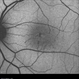

- macular telangiectasia, macular telangiectasia type 2

- OCT Angiography image in a 51-year-old male with fogging of vision and leaking on fluorescein angiography.